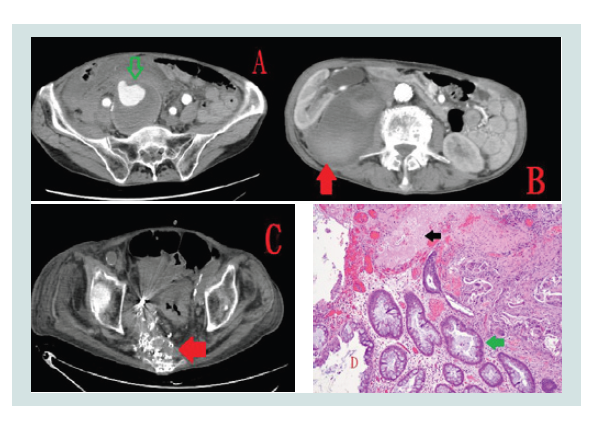

An 81-year-old man presented to the emergency department with a 2-week history of repeated bloody stools. In March 2015, he had right internal iliac artery aneurysm rupture (Panel A, arrow). He received EVAR and TAE in the distal internal iliac artery. In the next month, he had a retroperitoneal abscess, which was confirmed by the presence of Escherichia coli in blood culture and computed tomography (Panel B, red arrow). In addition, computed tomography revealed right hydronephrosis. After he accepted percutaneous abscess drainage, he recovered well. However, he found that he had hematuria in October 2015. He underwent percutaneous nephrostomy to improve his symptom. Thereafter, he also underwent revision of the percutaneous nephrostomy tube monthly due to failure of the double-J stent setting. In September 2016, he developed sepsis due to E. coli infection. Moreover, he had repeated bloody stools since April 2017. He underwent a colonoscopic examination five times because we could not make a definitive diagnosis. Colonoscopy revealed a sigmoid colon ulcer and active bleeding. We could not finish the hemostatic procedure, so we suspected the formation of fistula between the aneurysm and the sigmoid colon. Consequently, computed tomography was arranged and revealed aneurysm involvement to the adjacent colon with possible fistula formation (Panel C, arrow). Therefore, he underwent operation with the Hartmann procedure. The pathological report demonstrated that the picture was compatible with aneurysmo-colonic fistula (Panel D, black arrow: aorta wall, green arrow: colon).